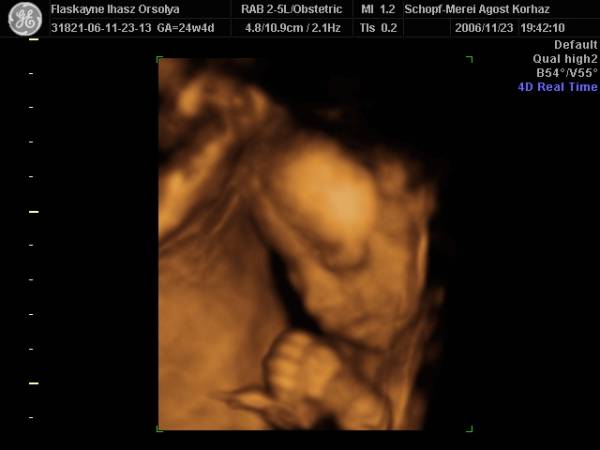

És aznap délután 4D!!!